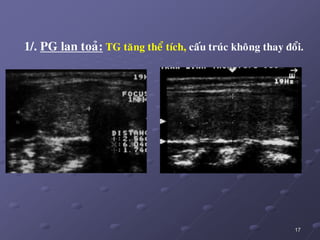

1/. PG lan toaû: TG taêng theå tích, caáu truùc khoâng thay ñoåi.